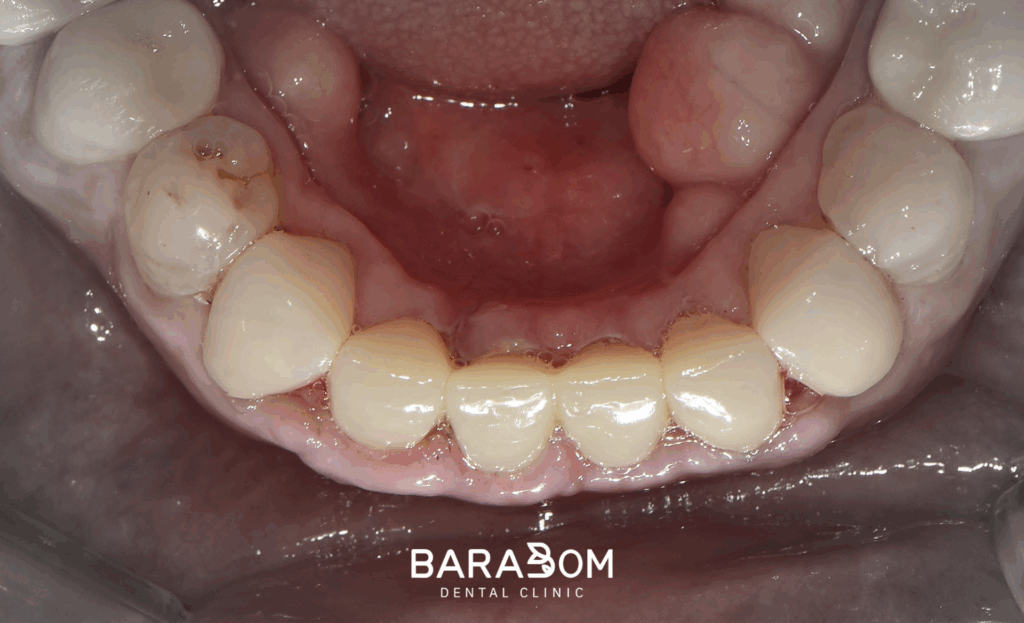

골 삭제와 더불어 포스트를 세워줌으로써 충분한 강도를 되찾아줌과 동시에 코어를 수복하여 길이를 확보하여 지대치 형성이 마무리되었습니다.

지대치 형성이 끝난 후, 정밀하게 본을 떠 기공 작업에 들어갑니다. 앞니 교합 관계를 고려하여 완성된 앞니 크라운이 완성되면 시적한 후 필요시 수정작업을 진행하고 접착제로 붙여주게 됩니다.

3. 치료 종결